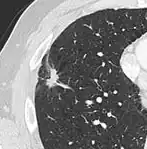

Thin slice and maximal intensity projection of a lung nodule, the latter better visualizing vascular convergence.[9]

• Vascular convergence is where vessels converge to a nodule without adjoining or contacting the edge of the nodule, and is mainly seen in peripheral subsolid lung cancers.[9] It reflects angiogenesis.[9]